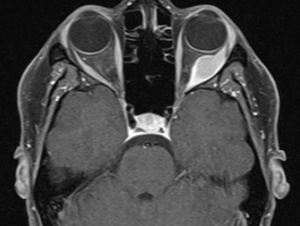

High-resolution orbital imaging is essential for the evaluation of suspected orbital GCTs. Both Computed Tomography (CT) and Magnetic Resonance Imaging (MRI) offer complementary information, with MRI generally favored for lesion characterization. The majority of infraorbital GCTs appear as well circumscribed, round lesions.[23] On CT, they appear as well-defined, homogeneous soft tissue masses that are isodense or mildly hyperdense to muscle.[8] Adjacent bony changes are uncommon, a finding better appreciated on CT.[23] On contrast-enhanced CT, GCTs typically show moderate, homogeneous enhancement.[23] On MRI, Orbital GCTs are generally isointense to gray matter on T1-weighted imaging and hypointense to isointense on T2-weighted sequences, a pattern that differs from most benign orbital tumors, which are typically T2-hyperintense.[8][23] MRI with gadolinium demosntrates slight to strong enhancement with avid peripheral enhancement (see image 1 and 2). [4][8] Diffusion weighted imaging generally does not show diffusion restriction.[23] ADC measurements have been investigated for use in differentiating benign from malignant lesions, however there is not a specific value which supports a diagnosis of GCT. [23]